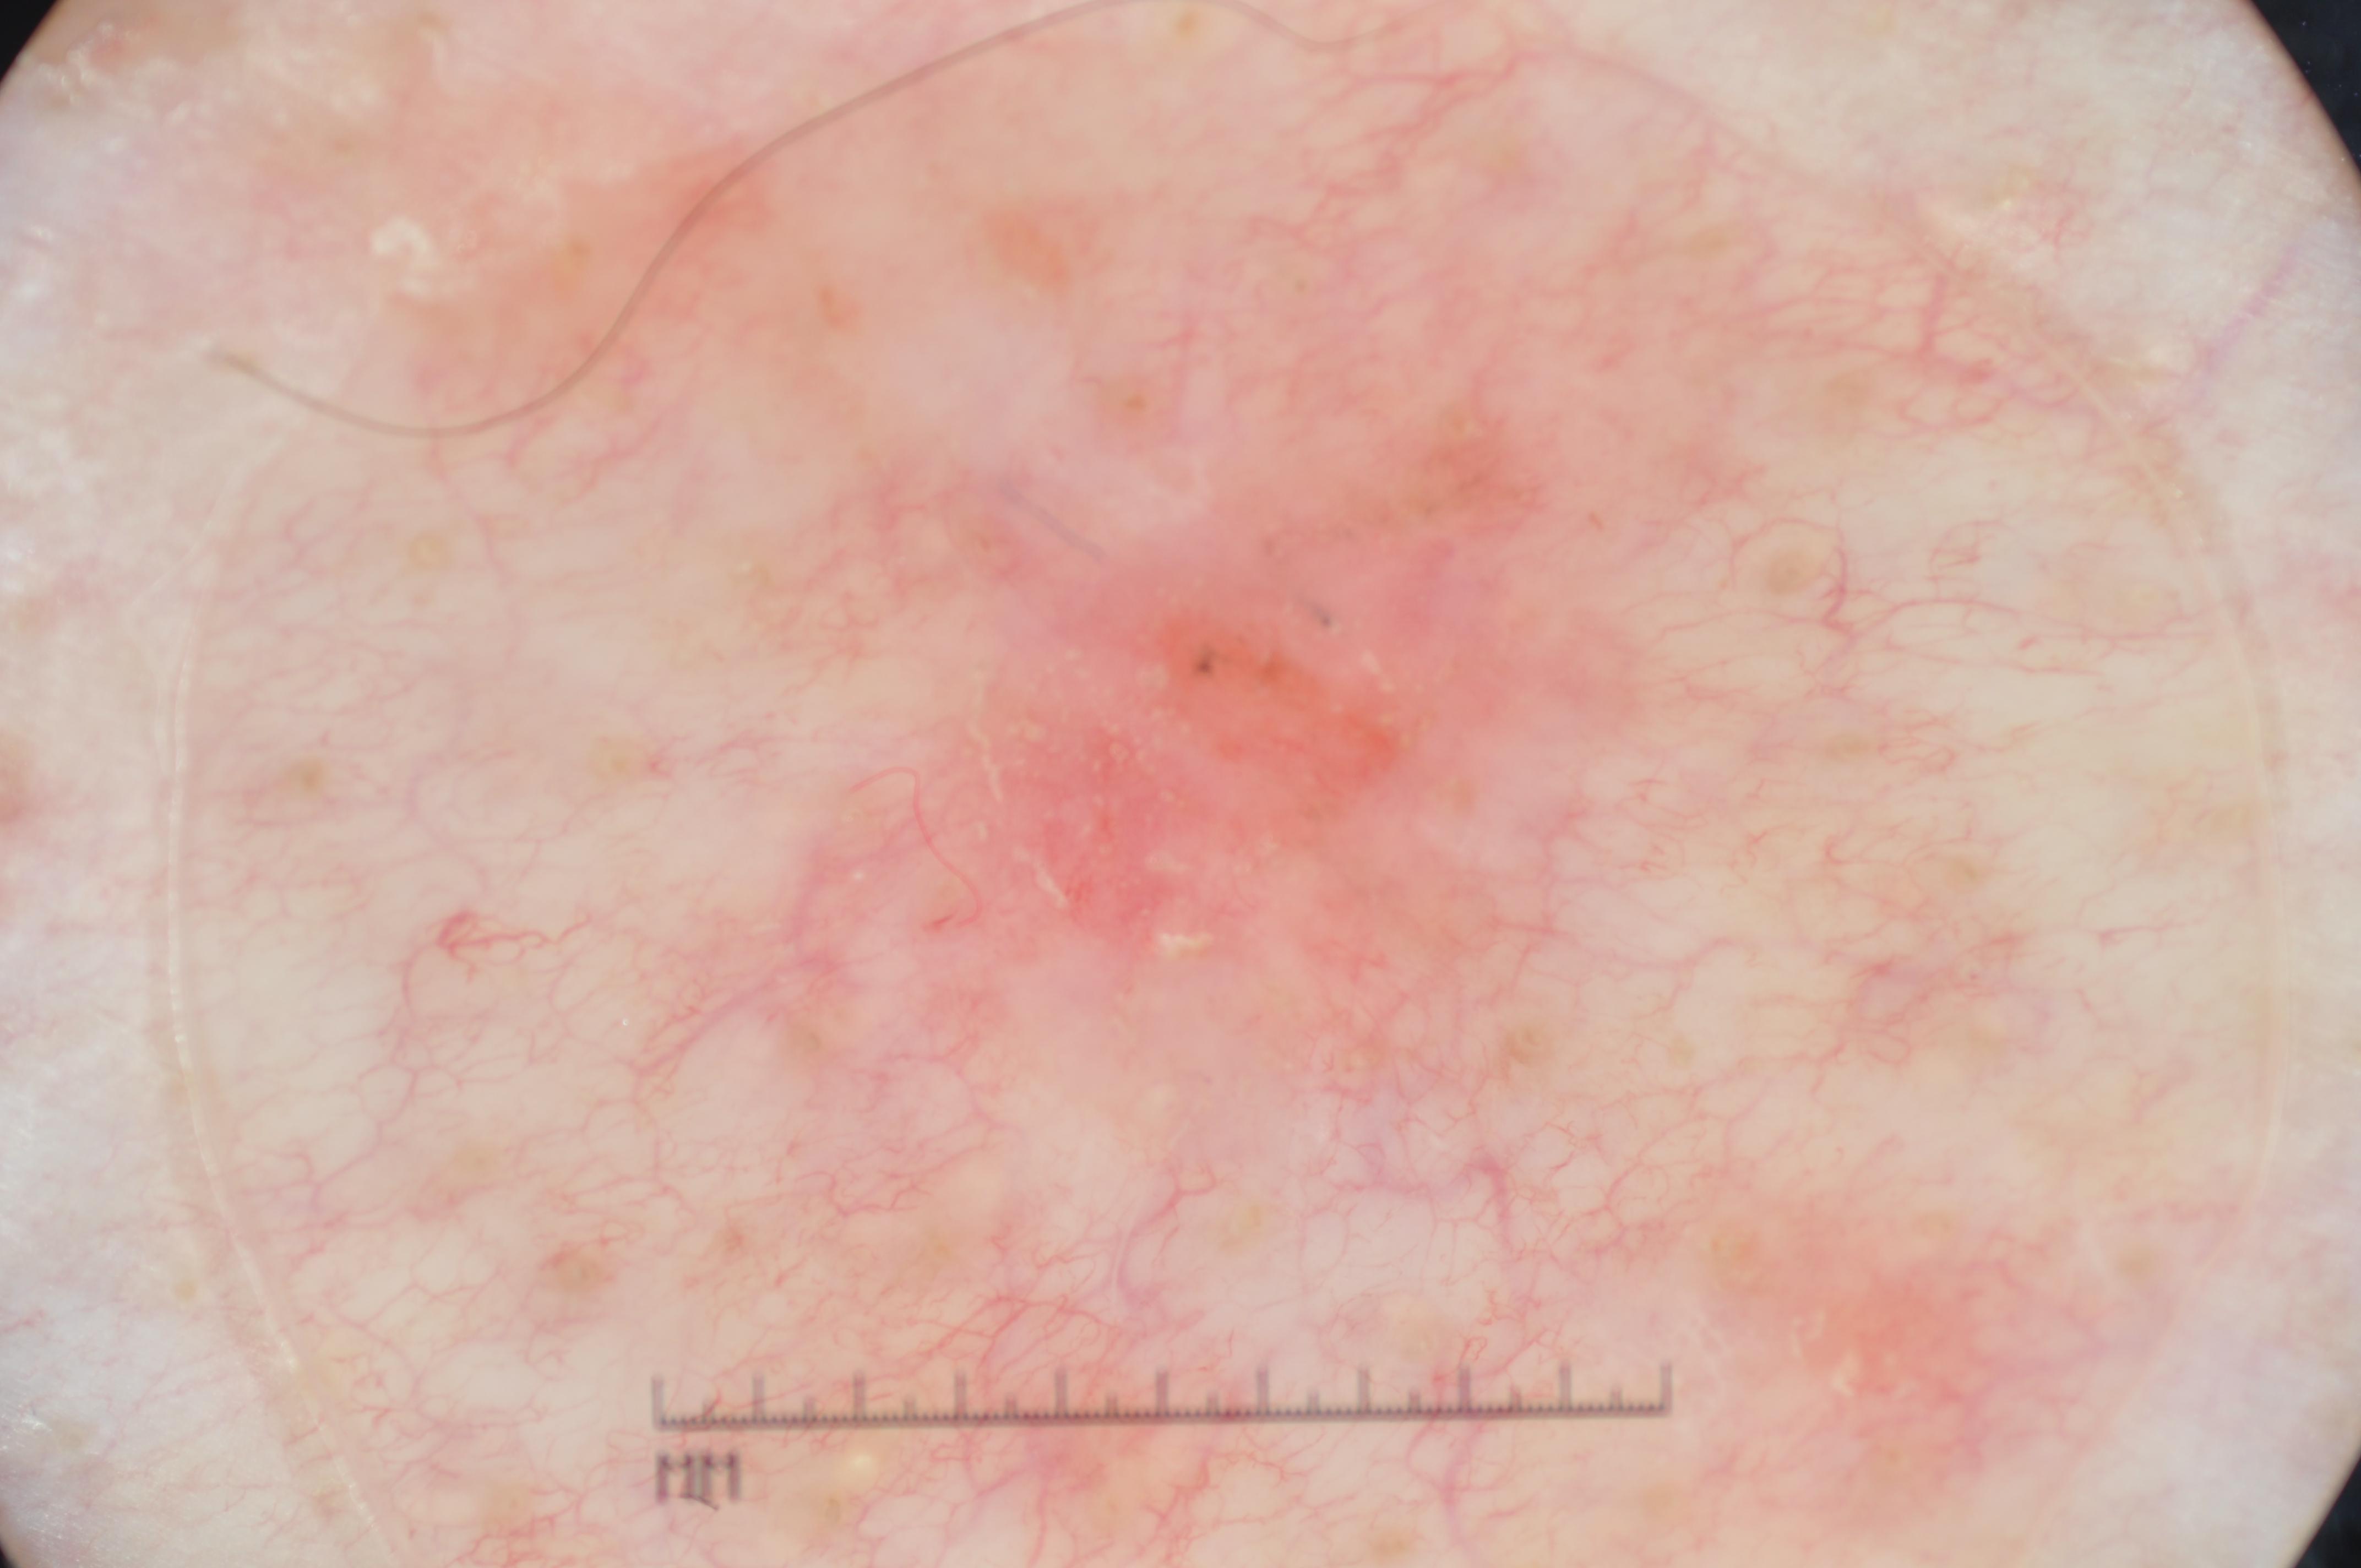

{

"age_approx": 60,

"anatom_site_general": "anterior torso",

"concomitant_biopsy": true,

"diagnosis_1": "Malignant",

"diagnosis_2": "Malignant adnexal epithelial proliferations - Follicular",

"diagnosis_3": "Basal cell carcinoma",

"diagnosis_confirm_type": "histopathology",

"image_type": "dermoscopic",

"lesion_id": "IL_2996464",

"melanocytic": false,

"sex": "male"

}